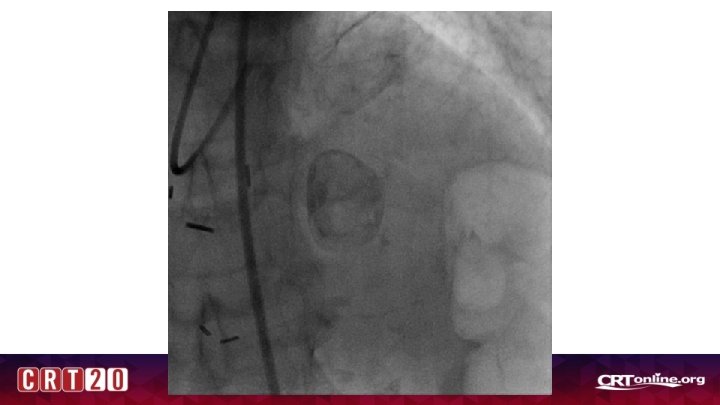

Case 1 • 77 yr old WF with PMN of osteoarthritis, osteoporosis, renal mass being monitored closely, hypothyroidism who presented with weakness, nausea, and atypical chest pain. Had several months of nonspecific periodic nausea leading up to admission. • BP 170/70, HR 75 • EKG: NSR, Normal EKG • Hgb 11. 3, Plt 195 • Cr 0. 80 • Trop 3. 00 > 3. 78 > 3. 66 • Referred for coronary angiogram for NSTEMI

Where is the culprit?